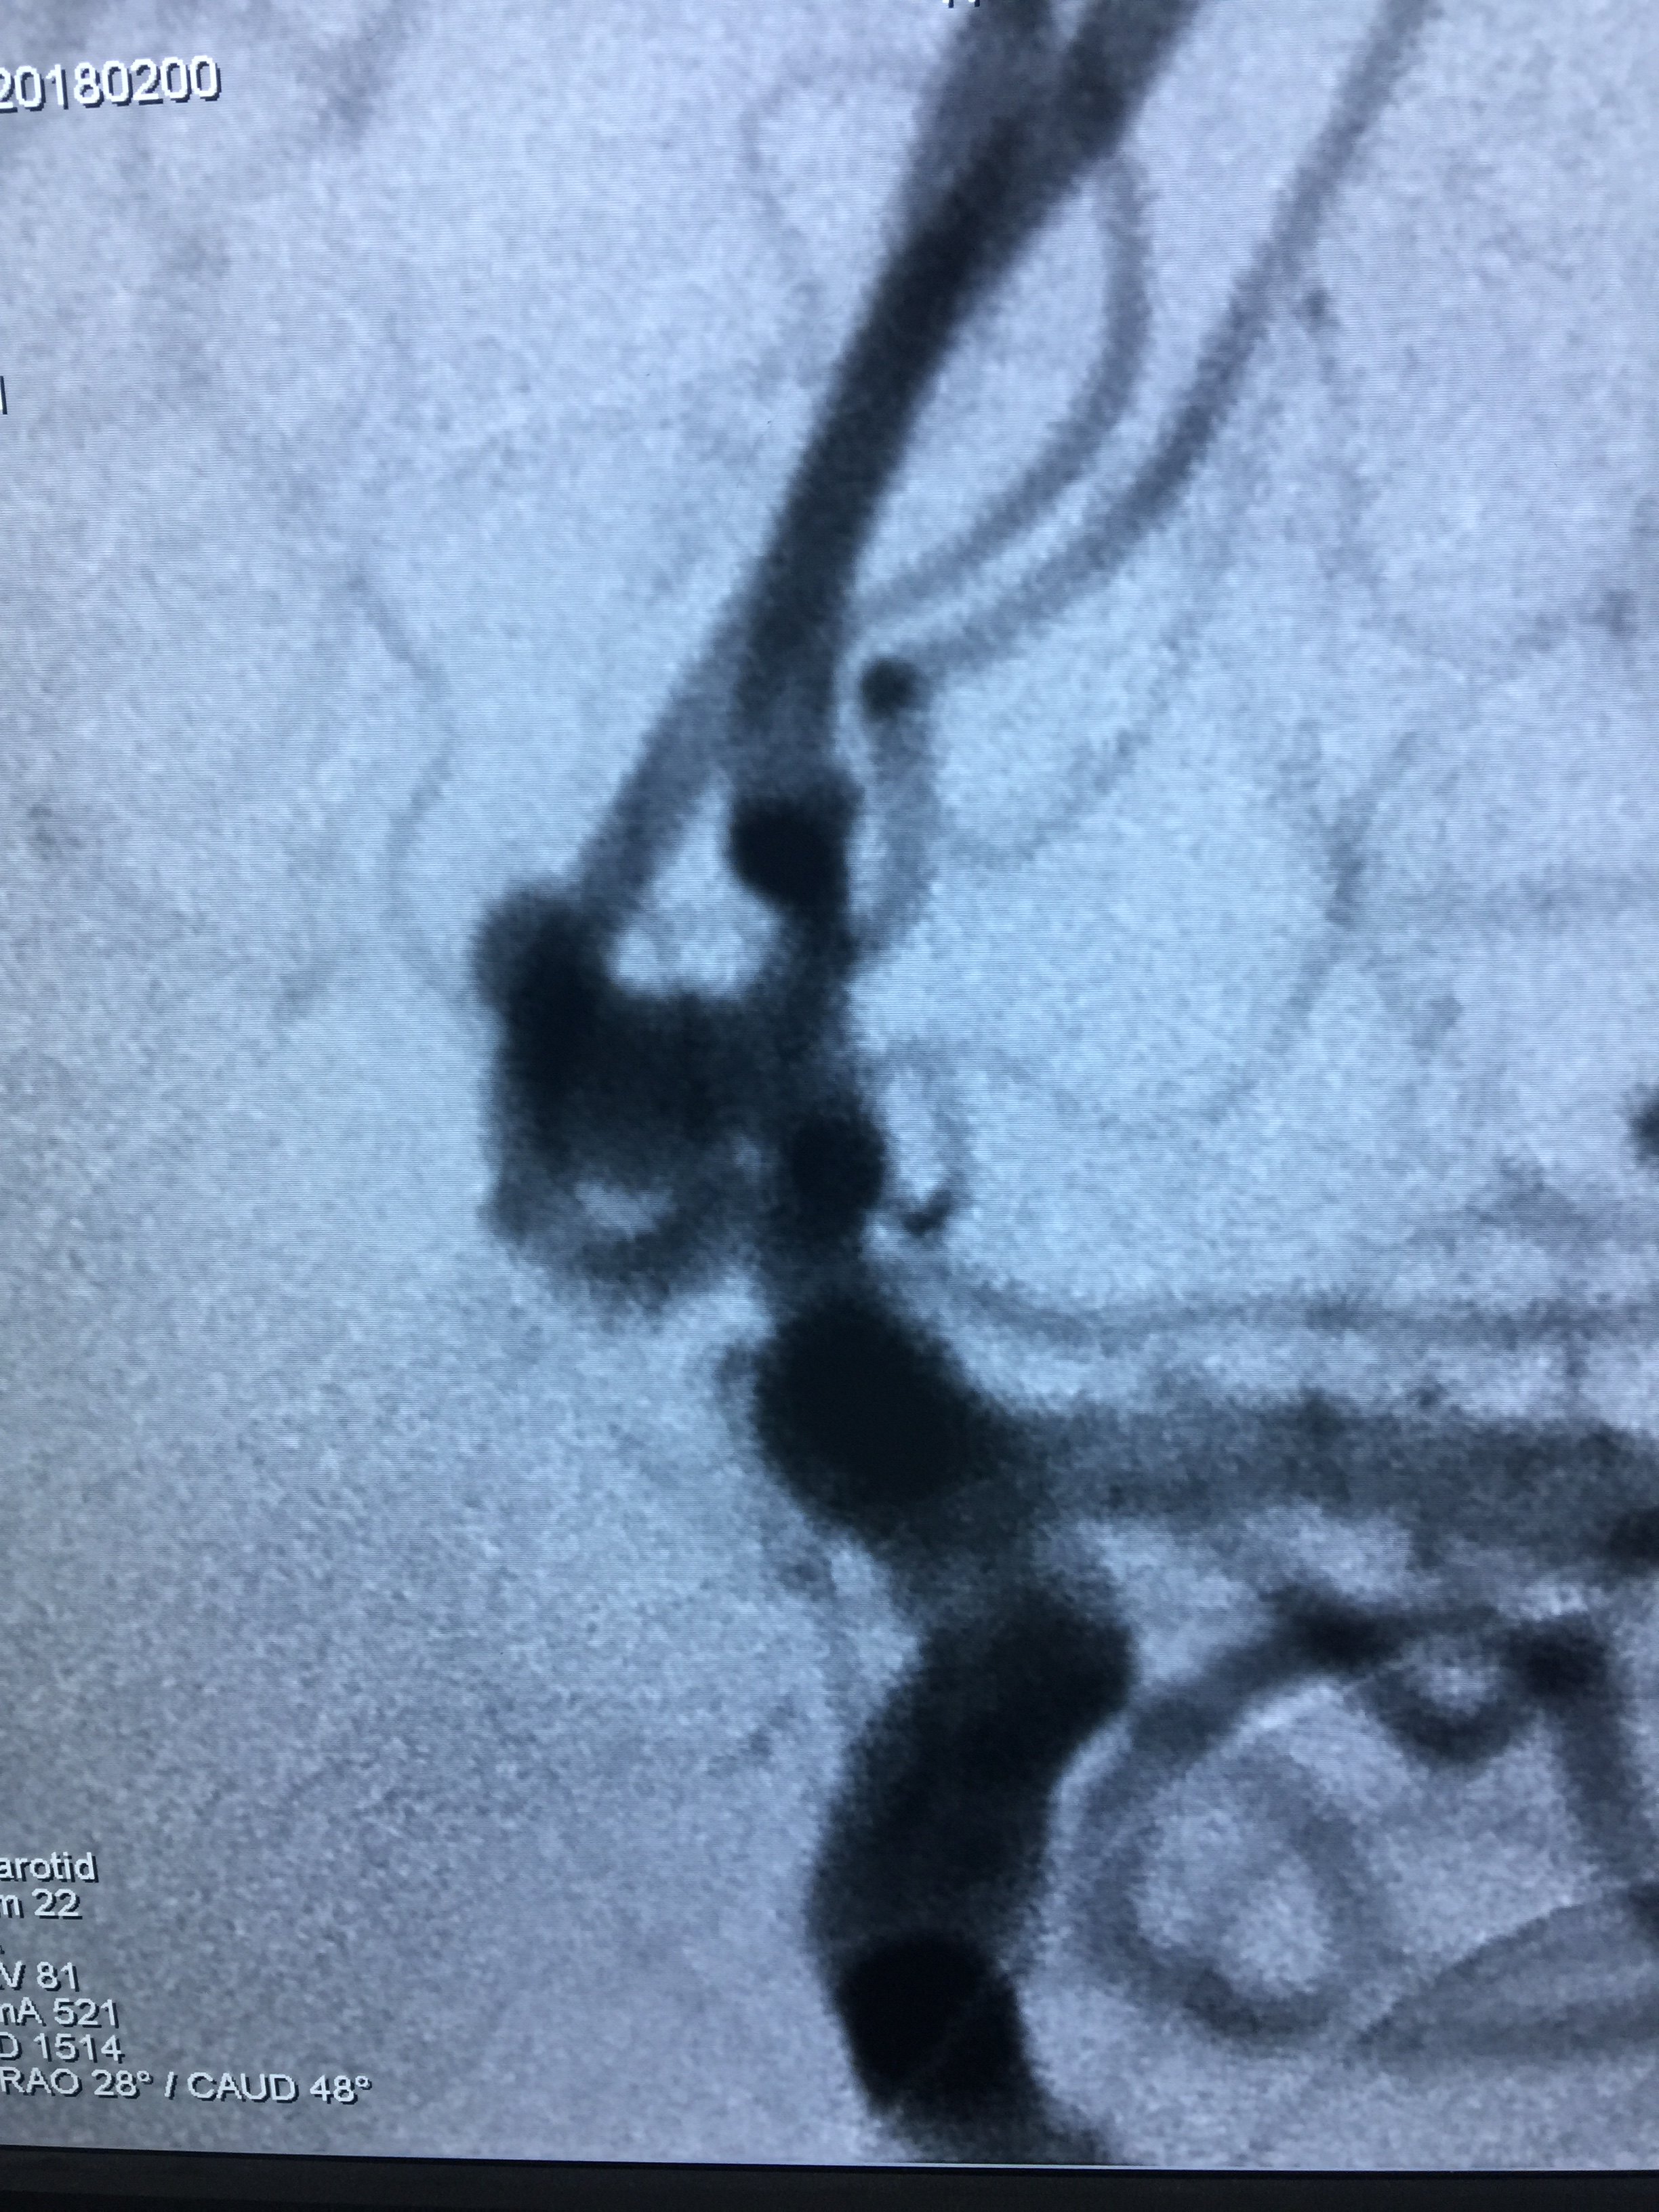

脑血管造影:前交通宽颈动脉瘤,血管迂曲,需要支架辅助栓塞